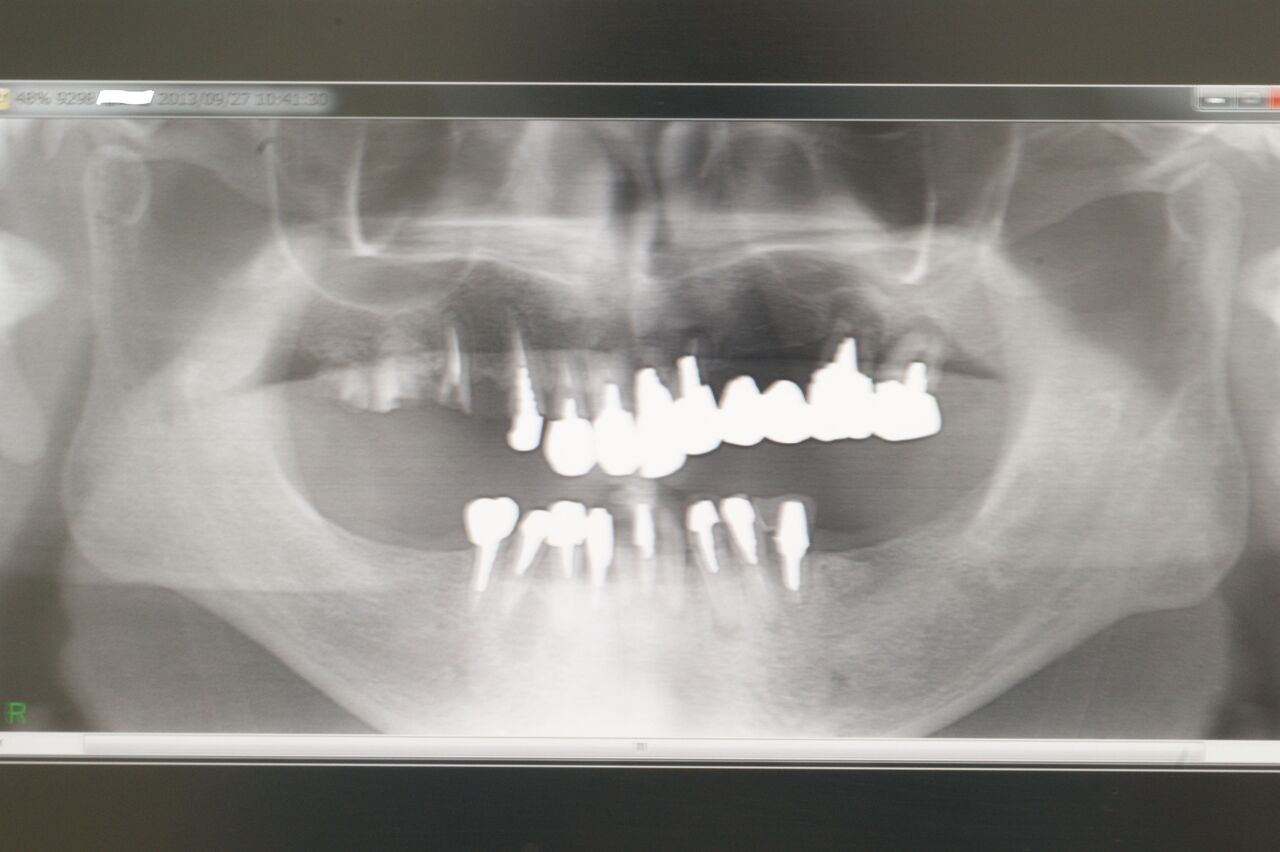

上のX線はある患者さんの初診時で、右上の脱離ブリッジを主訴として来院され、下顎には既に部分床義歯が装着されていました。

上顎は残存歯3本、インプラントでなく部分義歯を装着すれば、将来総義歯に移行するであろうことは火を見るよりも明らかです。インプラントによって、咬合の確立ができただけでなく、残存歯の寿命を延ばしめたところに、最大の意義があるのではないかと考えています。(大)